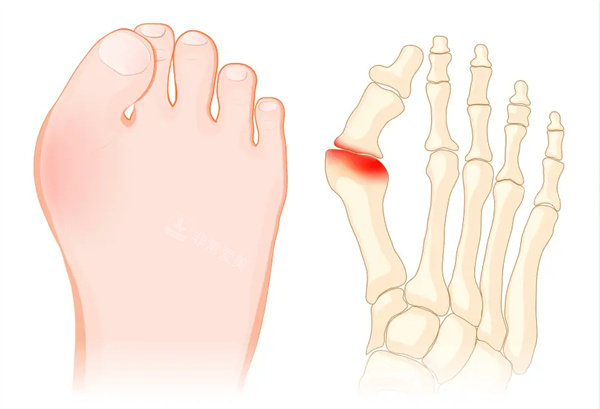

大脚骨外翻程度

拇外翻的发生与多种因素有关,如遗传、长期穿着不合适的鞋子等。

随着病情的发展,患者的拇趾会逐渐向外倾斜,头一跖骨头内侧会出现明显的骨赘,还可能引发拇囊炎,导致红肿、疼痛。

严峻的拇外翻会影响足部的正常功能,使患者行走困难,甚至影响到膝关节、髋关节等部位的健康。